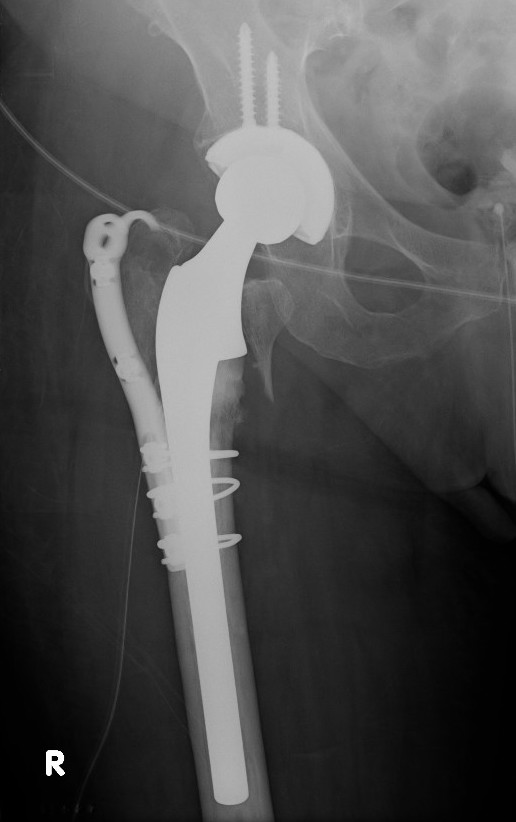

Hemiarthroplasty / Total hip replacement

Indications

- severe comminution

- salvage of failure of previous fixation

Technical

- may need calcar replacement

- may need greater trochanter fixation